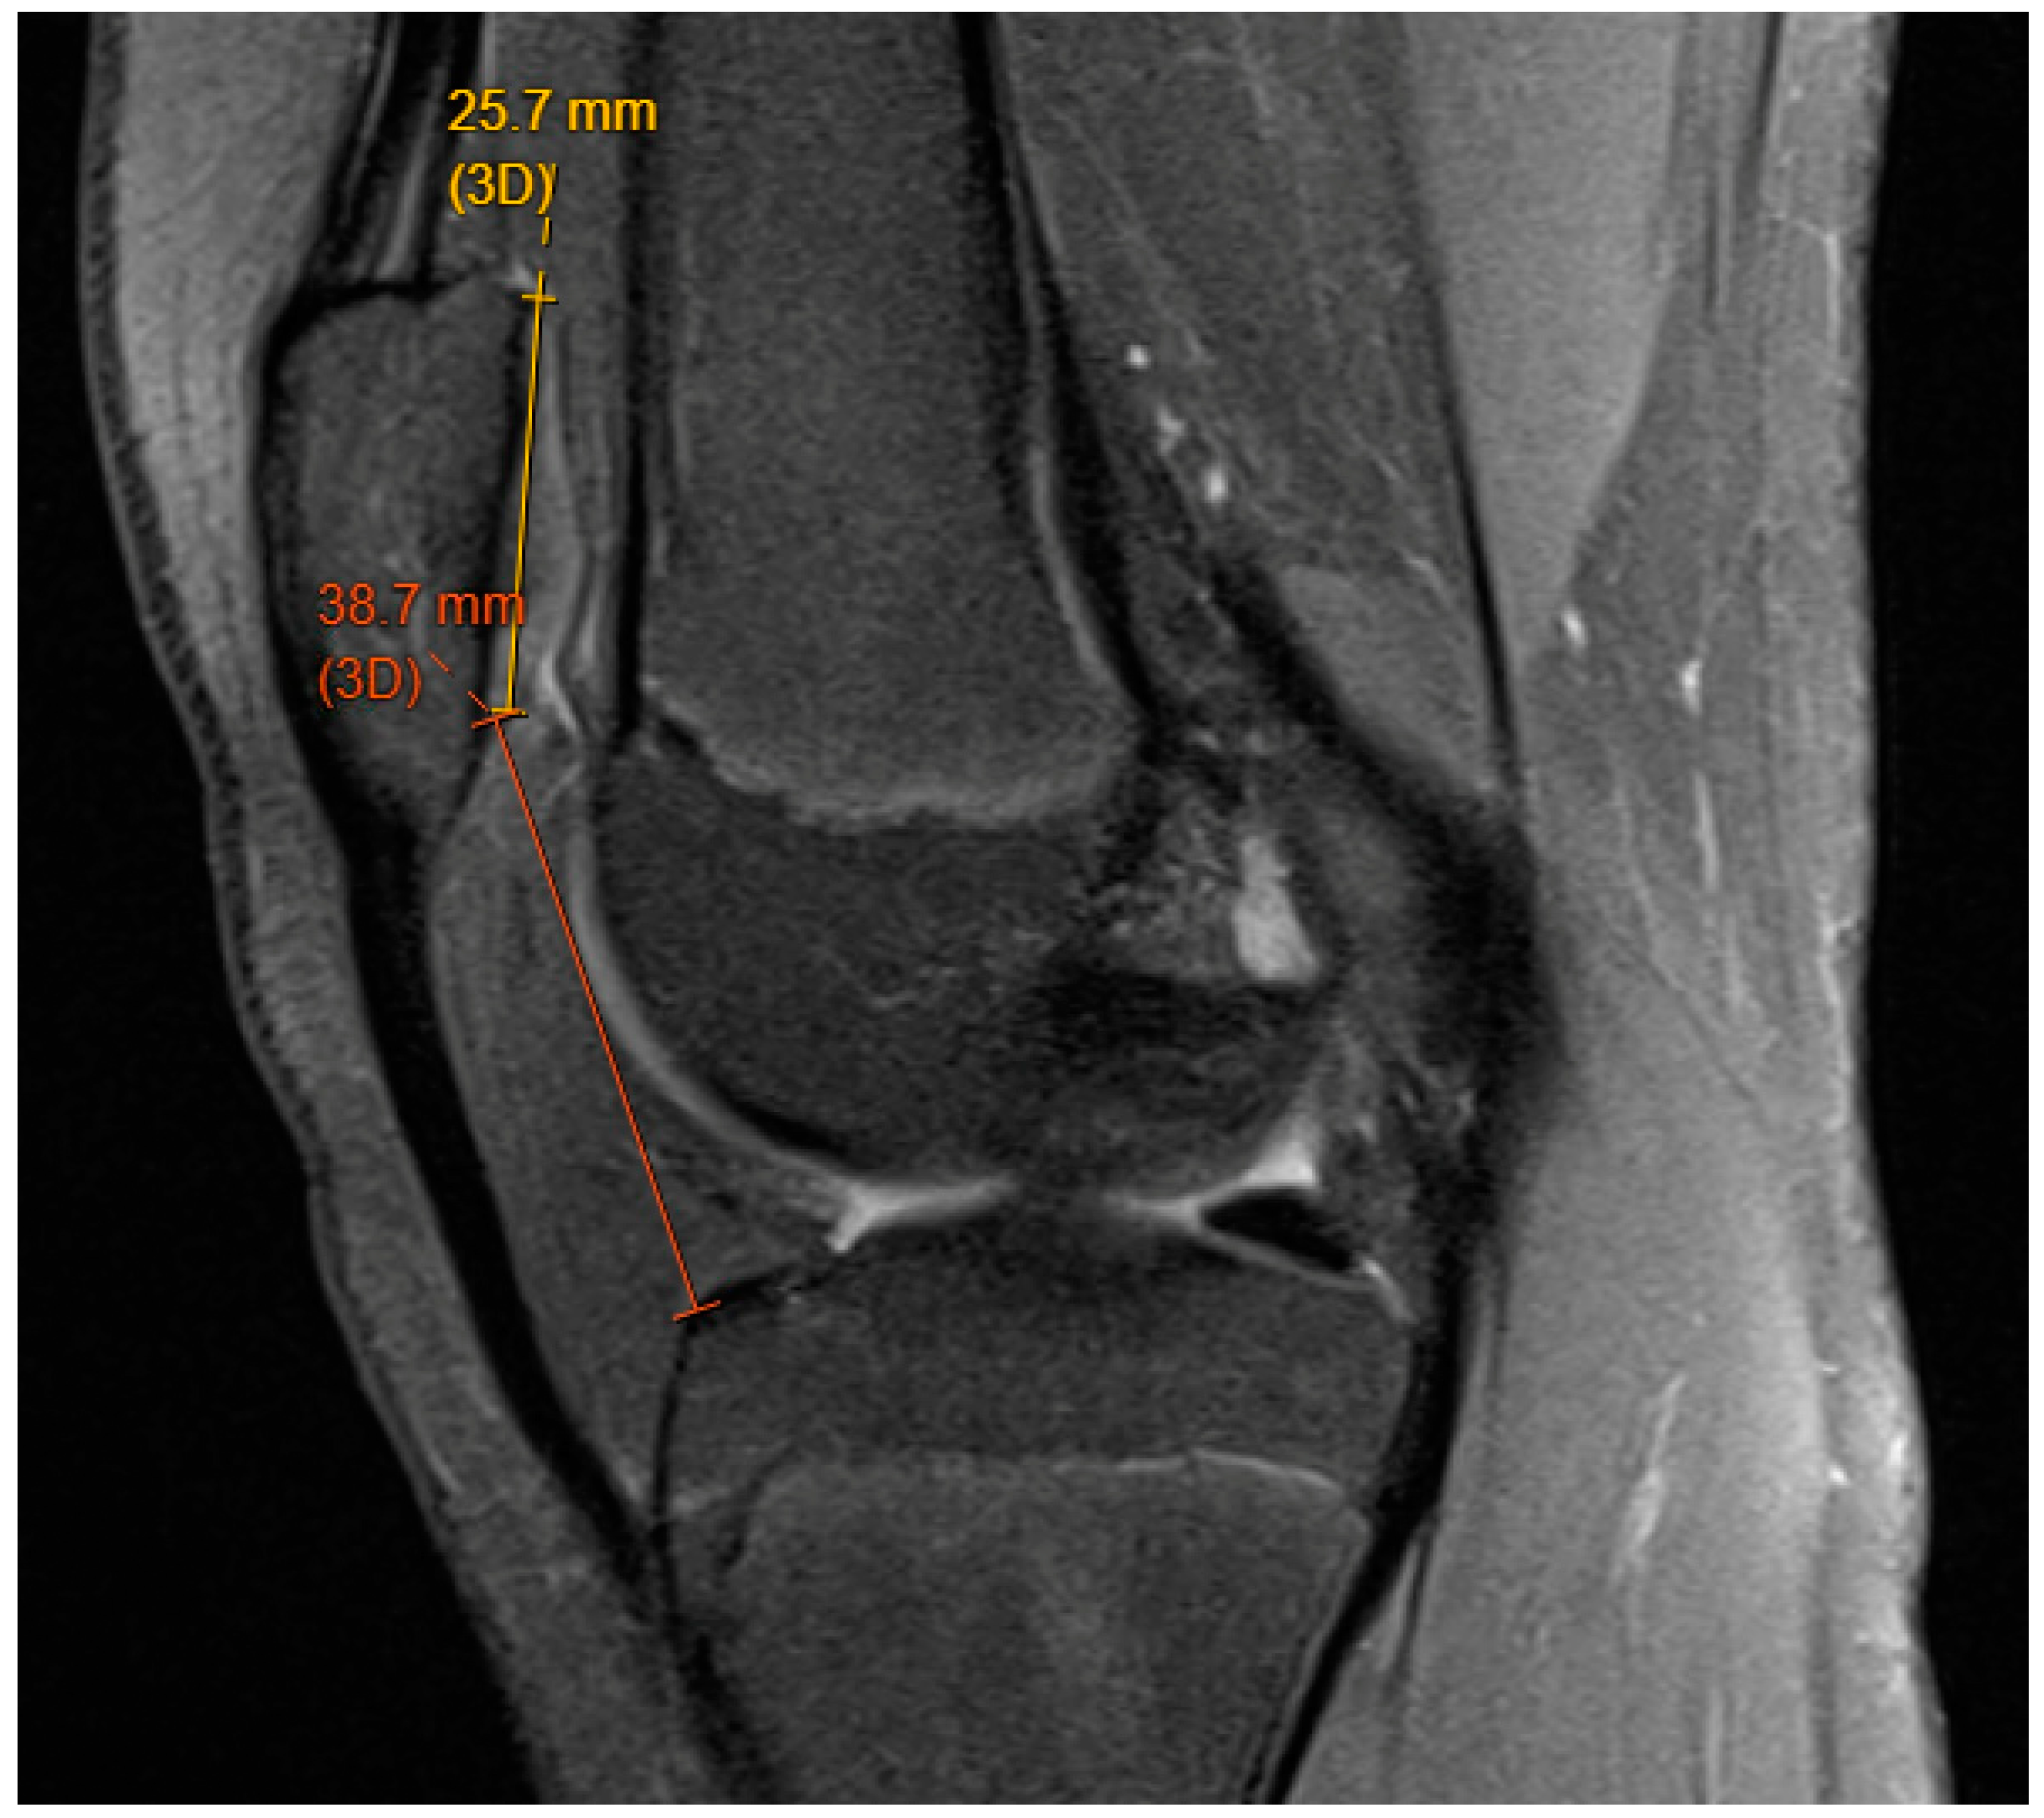

3.2. Patella Alta

8.5. Genu Valgum